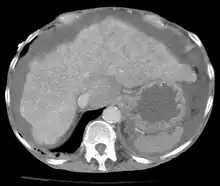

O aumento da quantidade de fluido peritoneal na cavidade peritoneal é conhecido como ascite (do grego askos, "saco"). A origem do líquido acumulado pode variar[1]:

Para confirmação da ascite, realiza-se ultrassonografia como exame de triagem, que revelará o aumento da quantidade de fluido na cavidade peritoneal e permite a escolha adequada do método e local para realização da paracentese. O método é geralmente seguro, mas riscos como desvio da agulha, perfuração de órgãos abdominais e processos hemorrágicos podem eventualmente ocorrer. Não se deve realizar a técnica em pacientes não-colaborativos, com infecções de pele ou gestantes[2].